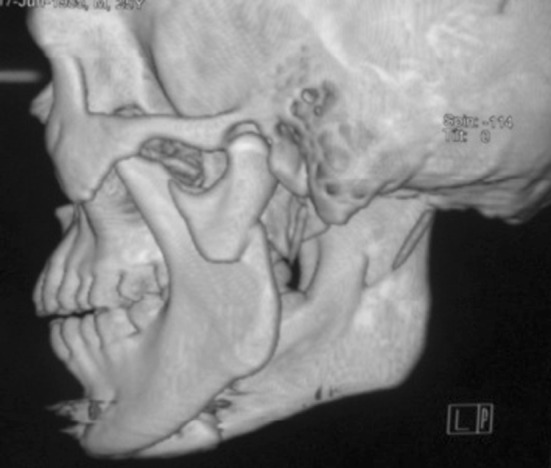

Fig. 7.

3D CT showing medially displaced left condylar fracture

Patients were operated under general anesthesia via preauricular and retromandibular approaches. Patients with fractured dislocation and displacement of mandible condyle in medial direction were managed by preauricular approach. Patients with lateral displacement of mandibular condyle were managed by retromandibular approach. Reverse towne’s and C.T. scan (Figss. 2 and 7) were taken in all the cases prior to surgery to assess the pattern of displacement. Titanium mini plate system was used in all cases for fixation of condylar fracture (Fig. 3).